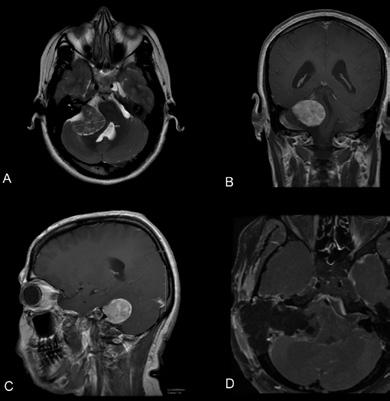

POZITIVNE FREKVENCIJE Godina dana rada Kardiohirurgije UKC RS Više od 200 spasenih života 8 JZU Bolnica „Sveti vračevi“ Bijeljina Vještačka inteligencija u medicini 10 Dr Milan Preradović, oftalmolog KVB i mikrocirkulacija retine 28 Dr Vladimir Cmiljanović, naučnik Inovacioni centar za nuklearnu medicinu 42 Dr sc. med. Nenad Živković Mikrohirurško lečenje akustičnog neurinoma 48 Dr sc. med. Slavica Žižić Borjanović Jedinstvena Olja Ivanjicki, umetnica 54 Medicinska revija Filozofija umeća uspešnog starenja 62 Dr Miodrag Manigoda, neurology Glavobolje 66 Info bilten UKC RS 79 Tradicionalno druženje Generacija studenata medicine 1972/77 90